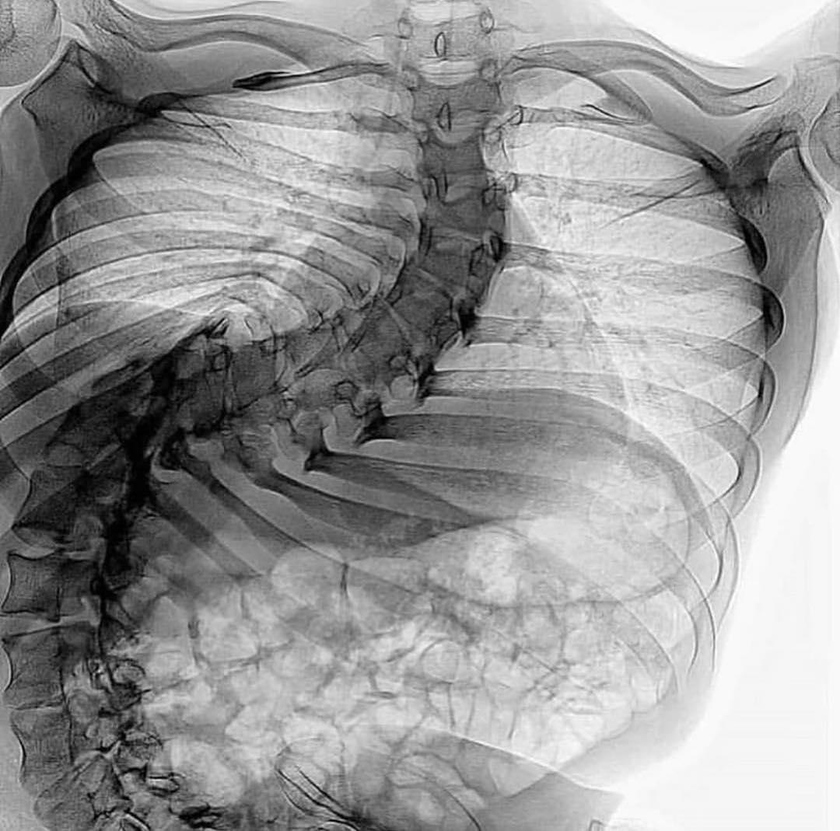

Сколиоз 4 степени.

Четвертая степень сколиоза. Наблюдается очень сильное искривление таза и туловища, выраженные задний и передний горбы.